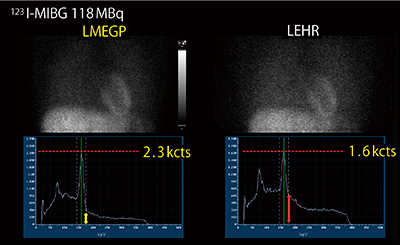

■真の汎用コリメータ“LMEGPコリメータ”

図4 LMEGPコリメータとLEHRコリメータの比較

(画像ご提供:国立循環器病研究センター様)